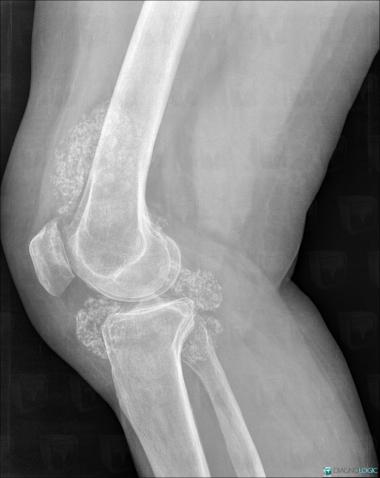

Ostéochondromatose synoviale, Articulations fémoro tibiales / Echancrure, Autres parties molles/nerfs - Genou, Radio

- Diagnostic Ostéochondromatose synoviale, Localisation(s) Articulations fémoro tibiales / Echancrure, comportant les gammes Arthropathie avec nodules des parties molles, Masse des parties molles juxta articulaires, Calcification intra ou périarticulaireAutres parties molles/nerfs - Genou, comportant les gammes Masse des parties molles juxta articulaires, Masse calcifiée des parties molles, Calcifications des parties molles